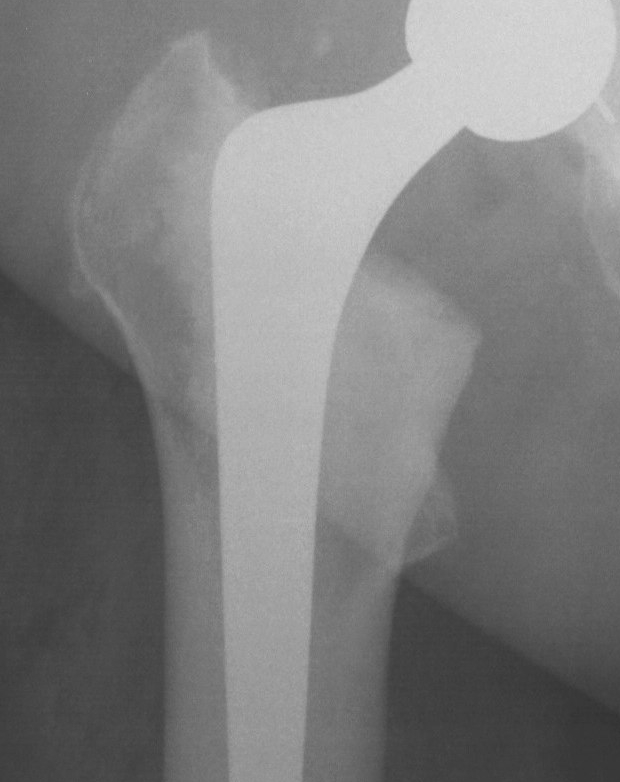

Barrack's femoral component cementation quality grading system

| Grade | Definition |

|---|---|

| A | Complete filling of the medullary canal, without radiolucent lines between the cement and the bone (white-out) |

| B | Radiolucent line covering up to 50% of the cement-bone interface |

| C | Radiolucent line covering between 50% and 99% of the cement-bone interface or incomplete cement mantle |

| D | Complete radiolucent line (100%) at the cement-bone interface and/or absence of cement distally to the end of the stem |

Grade A Grade B Grade C Grade D